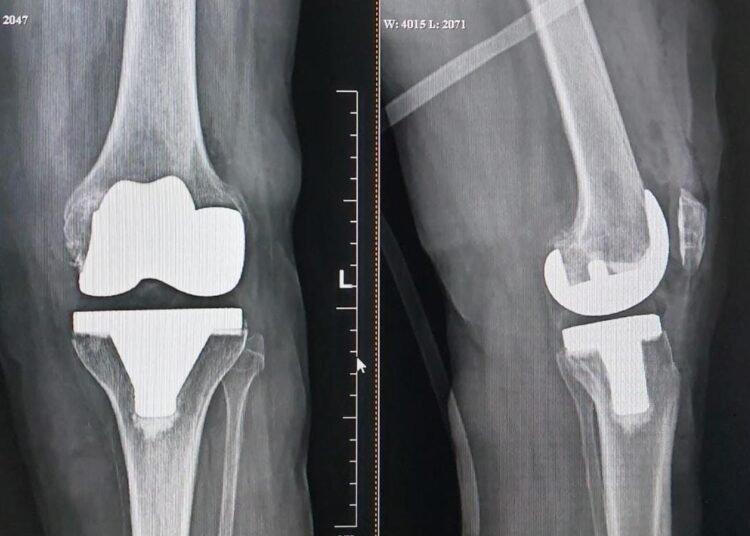

A team headed by Dr. Dhananjay Parab, Knee and Joint Replacement Surgeon at Zynova Shalby Hospital, Mumbai, successfully performed knee replacement surgery on a 78yr old woman suffering from severe osteoarthritis of both knees with ‘neglected club foot’. After undergoing the surgery, the women can stand on her feet again, and has resumed her daily routine now.

The patient was diagnosed with Club Foot but was not well managed. For the past 3-4 years she experienced sudden onset knee pain. Slowly, she found it difficult to carry on with her daily activities. As advised by a local doctor, the woman underwent X-rays of both legs. On medical examination, the doctor said that there is wear and tear in both knees. As the pain became unbearable, the family brought her to Zanova Shalby Hospital for treatment.

Dr. Dhananjay Parab, Knee Replacement Surgeon, Zynova Shalby Hospital, Mumbai said, “The woman could not walk due to severe pain and deformity in both her knees. In the medical report, it has been seen that the knee of the left leg of this woman has been damaged. In such a situation knee replacement surgery was the only option. In this regard, the surgery was performed with the permission of the family. The woman was able to stand on her feet again just hours after the surgery. Two days after the surgery, the woman was discharged.”

Dr. Parab added, “The woman was born with club foot, however it was not treated well, leading to a deformed foot. In such a situation, the problem of arthritis arises in the future. She had knee problems comparatively early due to club foot. Apart from this, the woman was suffering from diabetes and high blood pressure. Under such conditions, doing knee replacement surgery was a challenge. Yet, In this scenario doctors performed a successful knee replacement surgery”.